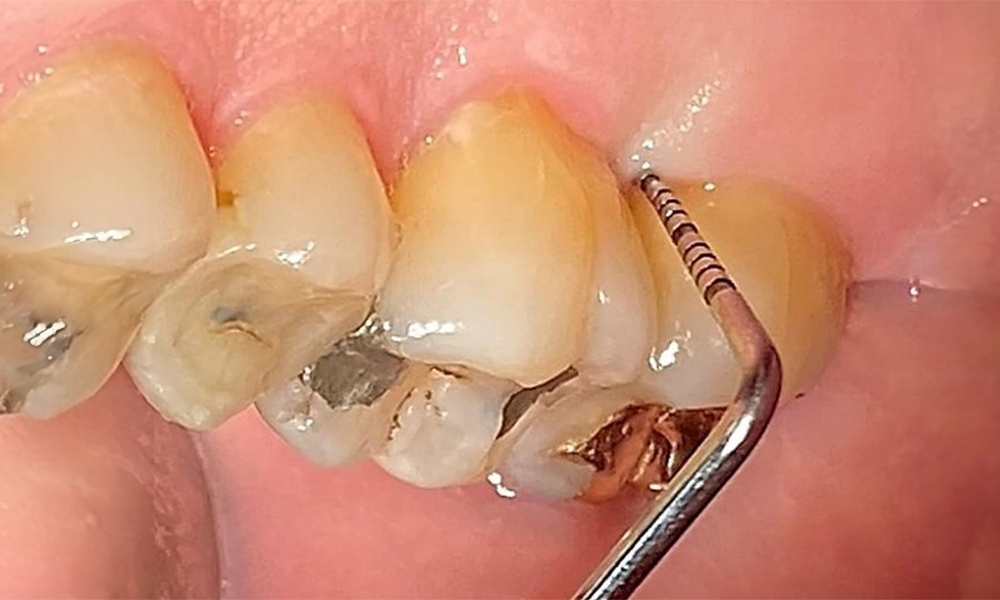

Der Patient hat ein vollbezahntes Gebiss mit 28 Zähnen, an welchen sich im Molaren- und Prämolarenbereich Amalgamfüllungen und Compositefüllungen befinden. An Zahn 14 zeigt sich ein sichtbarer klinischer Randspalt. Zahn 27 hat ein suffizientes Goldinlay. Zudem zeigen sich generalisierte Attritionen und Abrasionen. (Abb. 2, Abb. 3, Abb. 4, Abb. 5, Abb. 6)

Der Patient hat eine Parodontitis Stadium II, Grad B (5). Die klinischen Sondierungstiefen liegen mit 1-3mm im physiologischen Bereich. Lokalisierte Sondierungstiefen finden sich an 17 und 27 jeweils mesiopalatinal mit 5mm. Es liegen generalisierte Rezessionen von 1-3mm vor mit partiellem Verlust der Interdentalpapillen (Abb. 2, Abb. 3, Abb. 4)